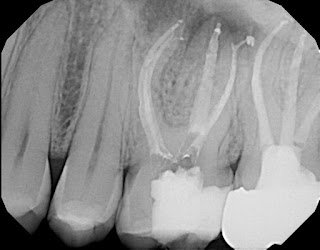

One of the biggest claims made regarding the GentleWave technique is “improved removal of organic matter” and creating a “higher standard of clean”. Evidence provided for this claim are usually images of more complex anatomy picked up when the tooth is obturated. The advocates call this “the thrill of the fill”.

However, the idea of cleaning and filling lateral canals and isthmuses is not unique to GentleWave. In our practice we have used both ultrasonic and sonic activation of irrigating solutions which has provided 3D cleaning and shaping of complex canal anatomy.

I have included several radiographic that demonstrate the “Thrill of the Fill” routinely seen at SSE using sonic activation of irrigating solutions. After our hands on demonstration with the GentleWave, I began putting aside radiographs after using sonic activation and found that the fill results were equally impressive.